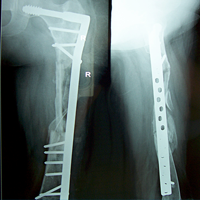

Case:2 GCT-L/E Radius

Pre-Op

Post-Op AP

Post-op Lateral